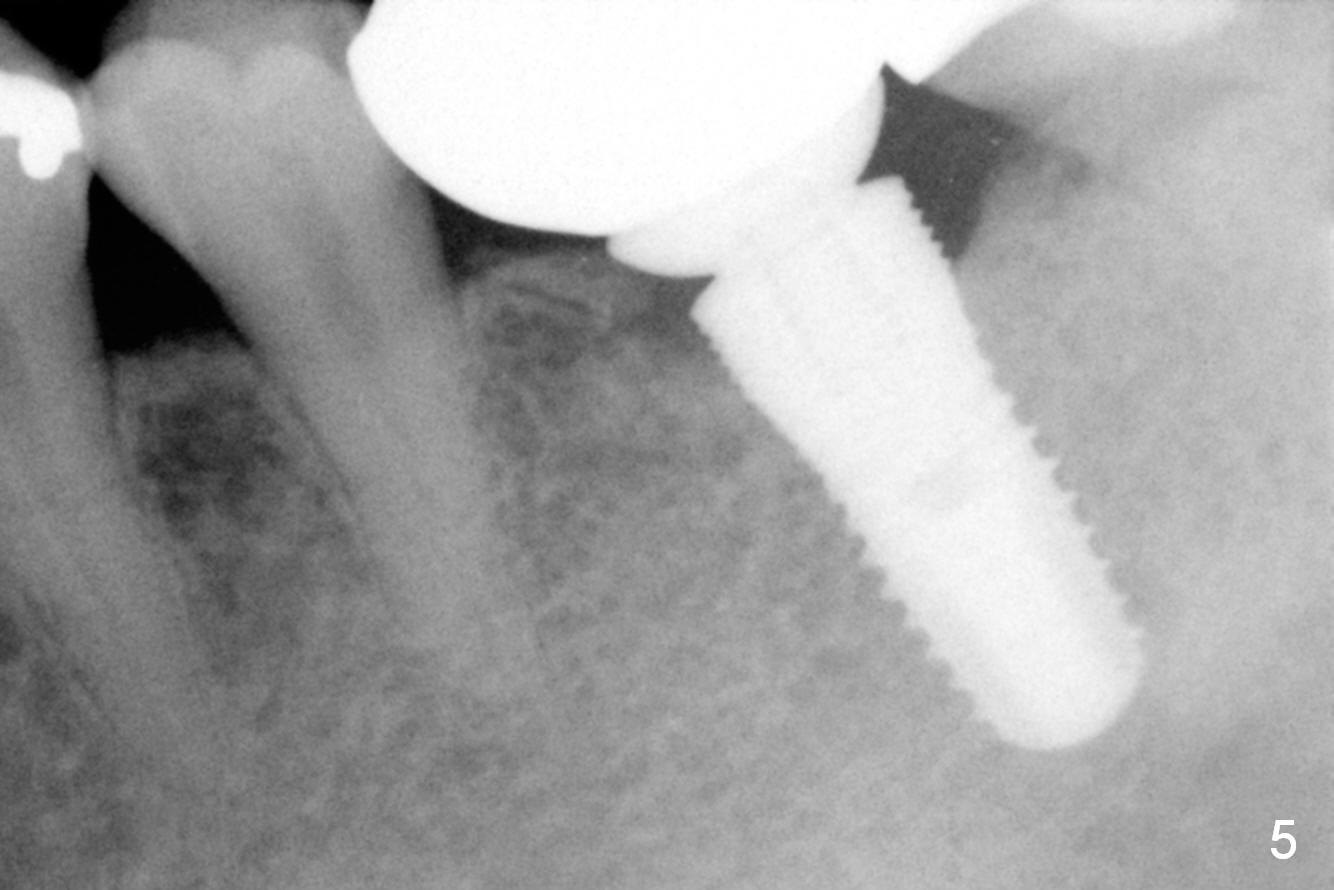

It appears that the diameter of the implant should be also controlled. A smaller implant may not lead to thread exposure and ultimately bone loss. It remains to be true 7 months post cementation (Fig.5). It appears that a 4.5 mm implant is better choice. There is no sign of periimplantitis. Oral hygiene, soft and hard tissues remains basically the same 2 years post cementation (Fig.6). The mesial open margin may be related to failure of impression material to get to the margin in spite of laser gingivectomy.